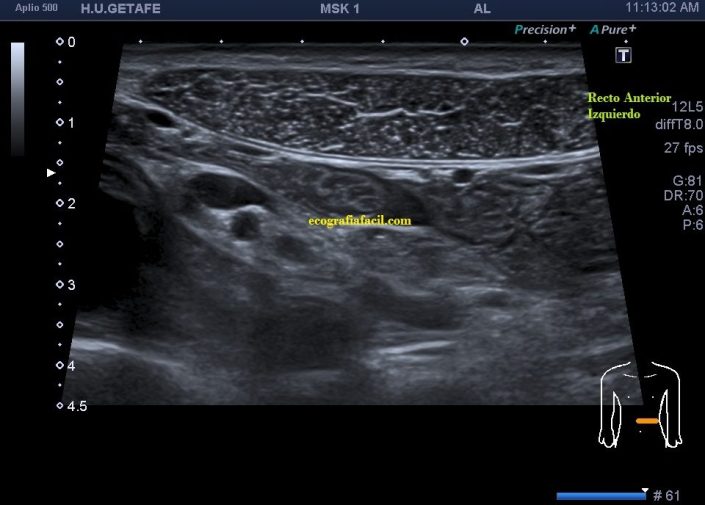

Durante la exploración se valoró la región de sospecha en mesogastrio izquierdo observando normalidad ecográfica, por contra, su lado contralateral me sorprendió presentándose como una estructura muscular anómala, hiperecogénica, atrófica con respecto al lado izquierdo.

En la imagen 3, segundo grupo muscular, puedes ver como el lado izquierdo es normal y el derecho está completamente atrófico tanto ecográficamente, como visualmente, como al tacto, por tanto, la sospecha del médico no era más que la normalidad en el lado izquierdo y el aspecto atrófico del lado derecho.

La imagen 6 y 7 es el detalle del segundo grupo muscular de los rectos anteriores para que observes las diferencias entre ambos y puedas valorar ambas semiologías.

En esta ocasión, lo destacable es que la normalidad era lo que a la palpación era sospechoso y que el lado derecho, que parecía normal a la exploración, era el patológico ecográficamente. Llama la atención como todo el grupo muscular derecho está disminuido de tamaño a expensas de una atrofia en el vientre del músculo, que se hace muy evidente en el segundo grupo muscular.